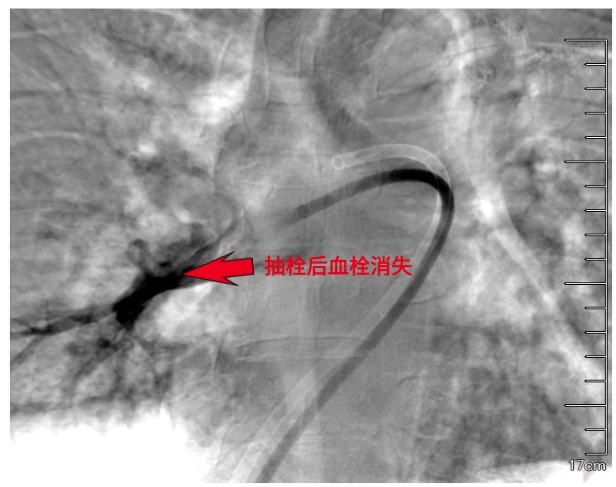

手术在现代化的杂交介入手术室进行。患者清醒地平卧在手术台上,医生在其腹股沟区消毒、局麻后,穿刺股静脉,送入一根比圆珠笔芯还细的导管。在X线透视的“实时地图”导航下,导管轻柔地经过心脏,直抵被血栓“堵死”的肺动脉主干。

医生将一种专用的大腔血栓抽吸导管沿导丝送至血栓内部。随着负压的启动,血栓被源源不断地吸入体外收集装置。术后即刻的肺动脉造影显示,先前中断的血流通道被重新打通,右心压力随之下降。这场在血管内部进行的“疏通作业”,安静而高效,没有开胸的惊心动魄,却完成了同样关键的使命。

精准靶向,直击病灶:在数字减影血管造影(DSA)的实时高清引导下,介入导管可被精确导航至肺动脉内的血栓部位,实现“指哪打哪”的精准治疗。通过专用的抽吸导管,可像“微型吸尘器”一样,将堵塞主干的血栓快速吸出,术中即可恢复肺动脉主干血流,患者血压、血氧常在数分钟内得到改善。